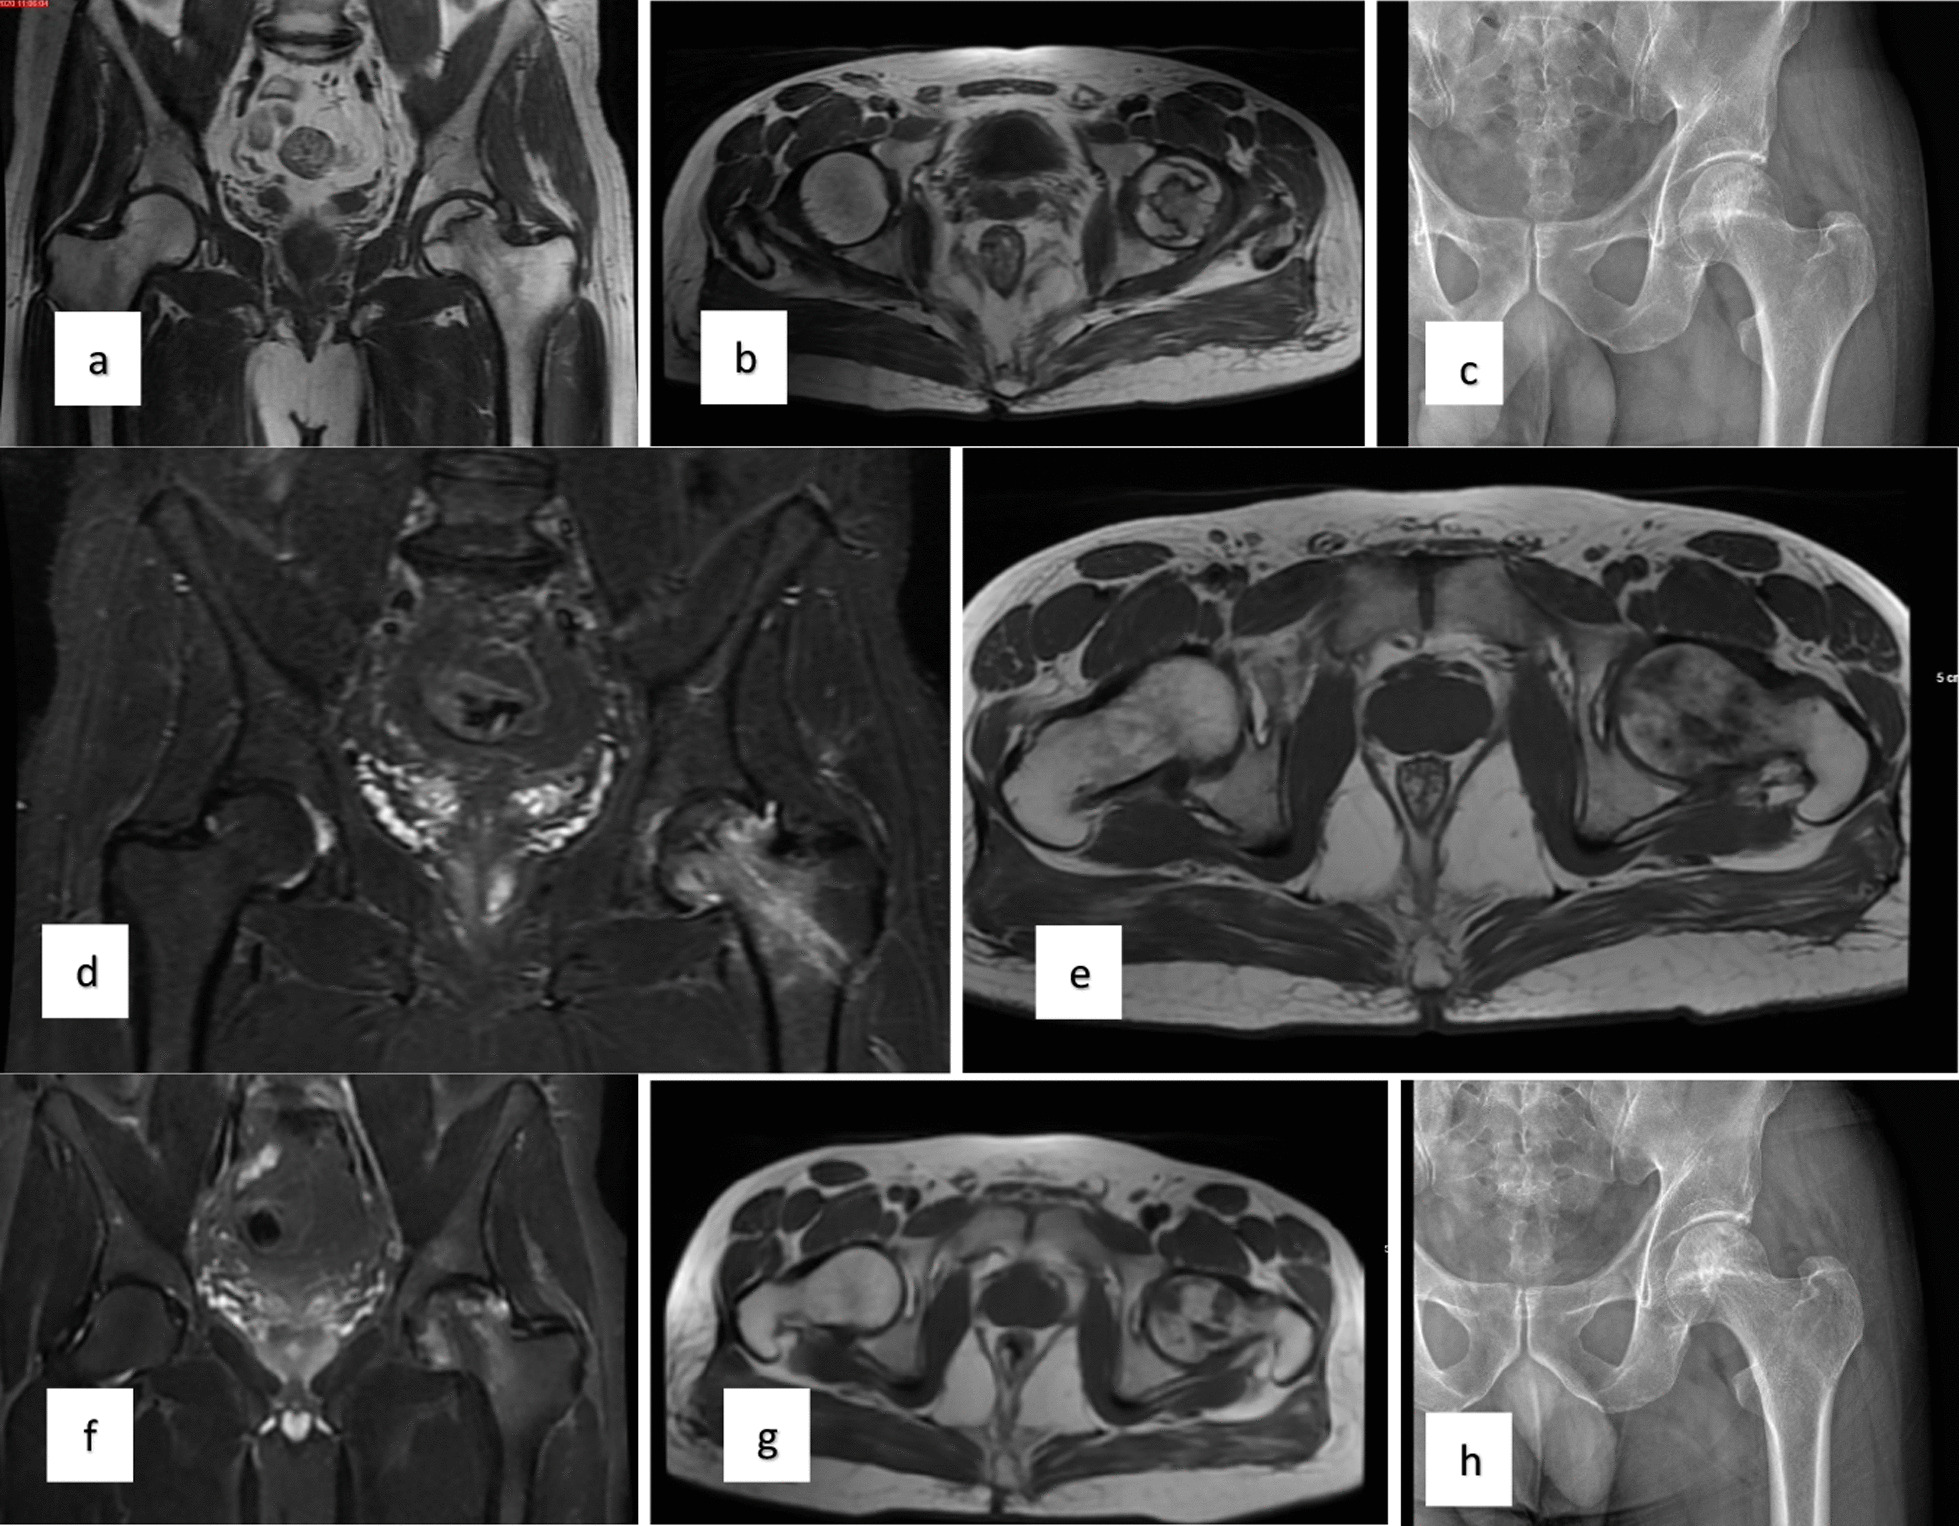

對(duì)患者的術(shù)前、3個(gè)月、6個(gè)月、1年和2年隨訪進(jìn)行評(píng)估(圖1)。

圖1:a–c左股骨頭缺血性壞死患者的術(shù)前MR和X射線圖像,d-e術(shù)后3個(gè)月的MR,f–h : 術(shù)后第二年的MR和X射線圖像